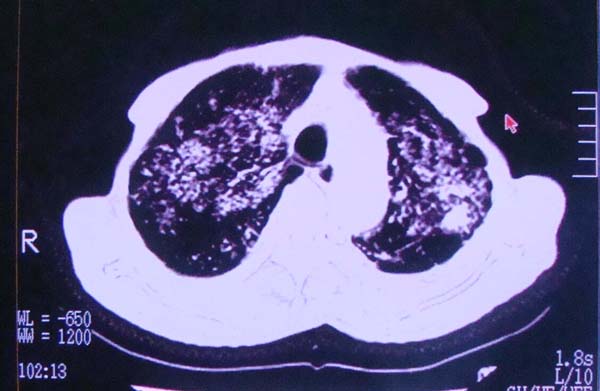

以下是引用zhangzhongshou在2008-2-15 22:25:00的发言:[br]片子照得不清,基本考虑1、细支气管肺泡癌2、亚急性血行播散型肺结核。请结合临床。片子细节显示不清,无法提供进一步意见。

以下是引用杀毒软件在2008-2-15 22:34:00的发言:[br]小叶中心性肺气肿。两肺弥漫性病变,肺泡微石病,过敏性肺炎,尘肺2期,特发性肺纤维化都有可能。[br]不象肺泡癌。